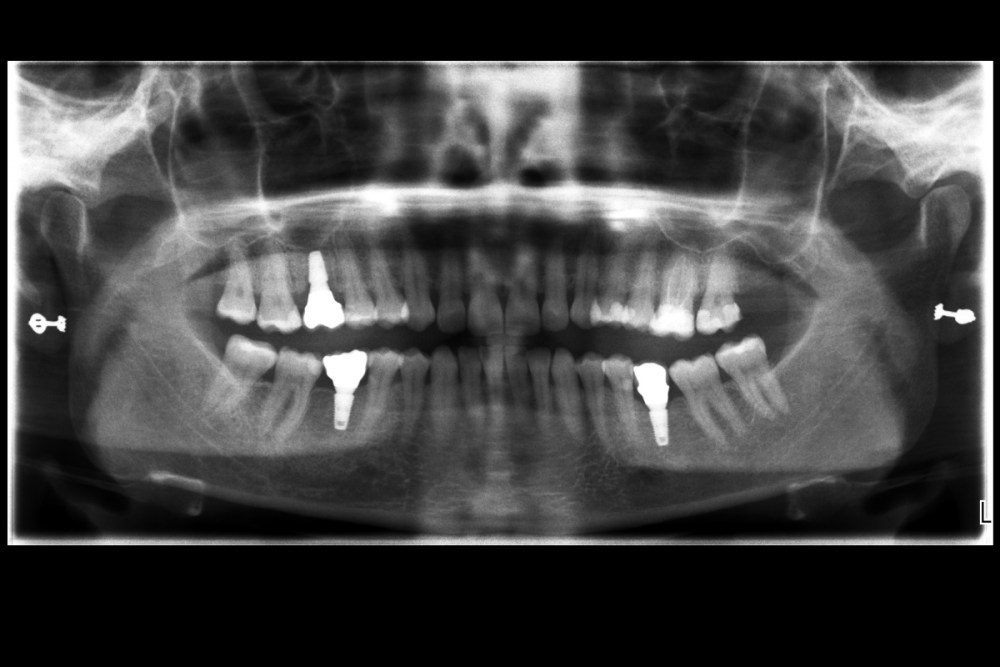

Карен Аванесов Опубликовано 10 ноября, 2021 Автор Поделиться Опубликовано 10 ноября, 2021 Придерживаясь правил форума, второе сообщение содержащее фотоматериал выдержанно в лучших традициях русской словестности, без сквернословия и непонятных иностранных слов, без применения шовного материала, широких формирователей десневой манжеты, без мягкотканной и прочей аугментации (наращивание костей что то все же не звучит прилично)), а самое главное, время затраченное на всю операцию 60 минут (имплантаты на нижней челюсти установил по лазерной технологии, без разрезов, Лазер - сила!). Время ожидания до ортопедического этапа 3 месяца. 6 1 Ссылка на комментарий

Марья Моревна Опубликовано 13 ноября, 2021 Поделиться Опубликовано 13 ноября, 2021 А что это такое кругленькое виднеется в лунке небного корня на самом левом из трех снимков над панорамой? 1 Ссылка на комментарий

Карен Аванесов Опубликовано 14 ноября, 2021 Автор Поделиться Опубликовано 14 ноября, 2021 13.11.2021 в 08:55, annda сказал: У инженера гиперболоид был, однако Не претендую на раскрытие секретов, видимо, что- то сакральное. Анна Анатольевна, в данном контексте, упоминание лазера, не более чем гипербола. Улыбайтесь чаще, Вам идет улыбка) 13.11.2021 в 20:19, Марья Моревна сказал: А что это такое кругленькое виднеется в лунке небного корня на самом левом из трех снимков над панорамой? А Вы Марья Моревна глазастенькая! Это воздушный пузырь, там две перфорации синуса, после удаления кисты. Ссылка на комментарий

Карен Аванесов Опубликовано 14 ноября, 2021 Автор Поделиться Опубликовано 14 ноября, 2021 (изменено) 13.11.2021 в 20:19, Марья Моревна сказал: А что это такое кругленькое виднеется в лунке небного корня на самом левом из трех снимков над панорамой? Это некий цимус-изюминка, в этой работе Изменено 14 ноября, 2021 пользователем Карен Аванесов Ссылка на комментарий